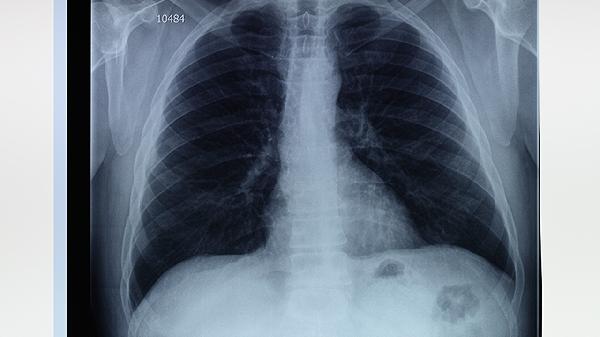

肺气肿可能由长期吸烟、空气污染、职业粉尘接触、遗传性α-1抗胰蛋白酶缺乏等原因引起,需通过肺功能检查、胸部影像学...